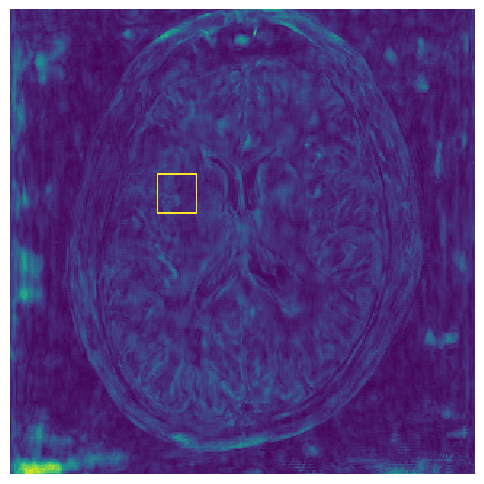

Figure 4: Uncertainty assessment. Scatter plots of the mean value of Std. estimate versus the MSE metric, calculated between the reconstructed and the ground truth, in log scale, for our NPB-REC method LABEL:sub@fig4:a and Monte Carlo Dropout LABEL:sub@fig4:b. LABEL:sub@fig4:c Our measure of uncertainty versus the acceleration rate.

5.2 Uncertainty Assessment

We calculated the mean value of the std. maps, obtained by our method and the Monte Carlo Dropout method, for all images in the inference set and utilized it as an uncertainty measure. The correlation between these uncertainty measures and reconstruction error (MSE) is depicted in Fig. 4. Our NPB-REC uncertainty measure exhibits a higher correlation with the Reconstruction error compared to Dropout (Pearson correlation coefficient of r=0.93𝑟0.93r=0.93 vs. r=0.89𝑟0.89r=0.89). Further, fig. 4LABEL:sub@fig3:c demonstrates our uncertainty measures correlate better with the acceleration rates used during acquisition. These outcomes, in turn, indicate the ability of our uncertainty measure to detect unreliable reconstruction performance. It is worth mentioning that the strong linearity of the correlation exhibited was preserved even for higher acceleration rates and when we repeated the same experiments on the knee test set (in all cases we obtained r>0.92𝑟0.92r>0.92).

Fig. 5 presents the uncertainty values measured in the cases of anatomical and undersampling mask distribution shifts. For the anatomical distribution shift, we considered the following scenarios: brain test set when the predictive model is trained on brain images as well (B-B), the same model tested on knee data (K-B), training and testing the model on the knee dataset (K-K) and the same model tested on brain data (B-K). Our uncertainty measures were significantly higher for the out-of-distribution cases compared to the within-distribution cases for both anatomical and undersampling mask distributions. In contrast, the uncertainty measures of Dropout method don’t show a significant difference in the case of anatomical shifts from knee to brain (see top-right part in Fig. 5).